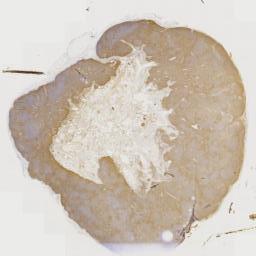

临床资料: 男,54岁,发现颈部两处肿物1年。双侧颈部局部探查:局部皮下软组织结构层次清晰,右侧颈部内可见一大小约24×8mm的淋巴结样回声,边界清,内回声不均匀血流信号,上述部位未见明显异常血流信号距体表约5mm。左侧颈部内可见数个淋巴结样回声,边界清,内回声不均匀,其中一个大小约6×5mm。CDFI:上述光团内及周边未见明感检查结果:双侧颈部软组织层异常占位(考虑淋巴结增大)。

大体所见: 灰白组织2枚,直径1.8-2.5cm,切面灰白。

免疫组化: 免疫组化:Ki-67(+),CD1O(+),CD20(+),Pax-5(+),CD3(+),CD5(+)。CD23(FDC网),Bcl-2(+),Bcl-6(+),MUM1(+),CD21(FDC网),CyclinD1(-),CD43(+),S-100(+),CD68(+).